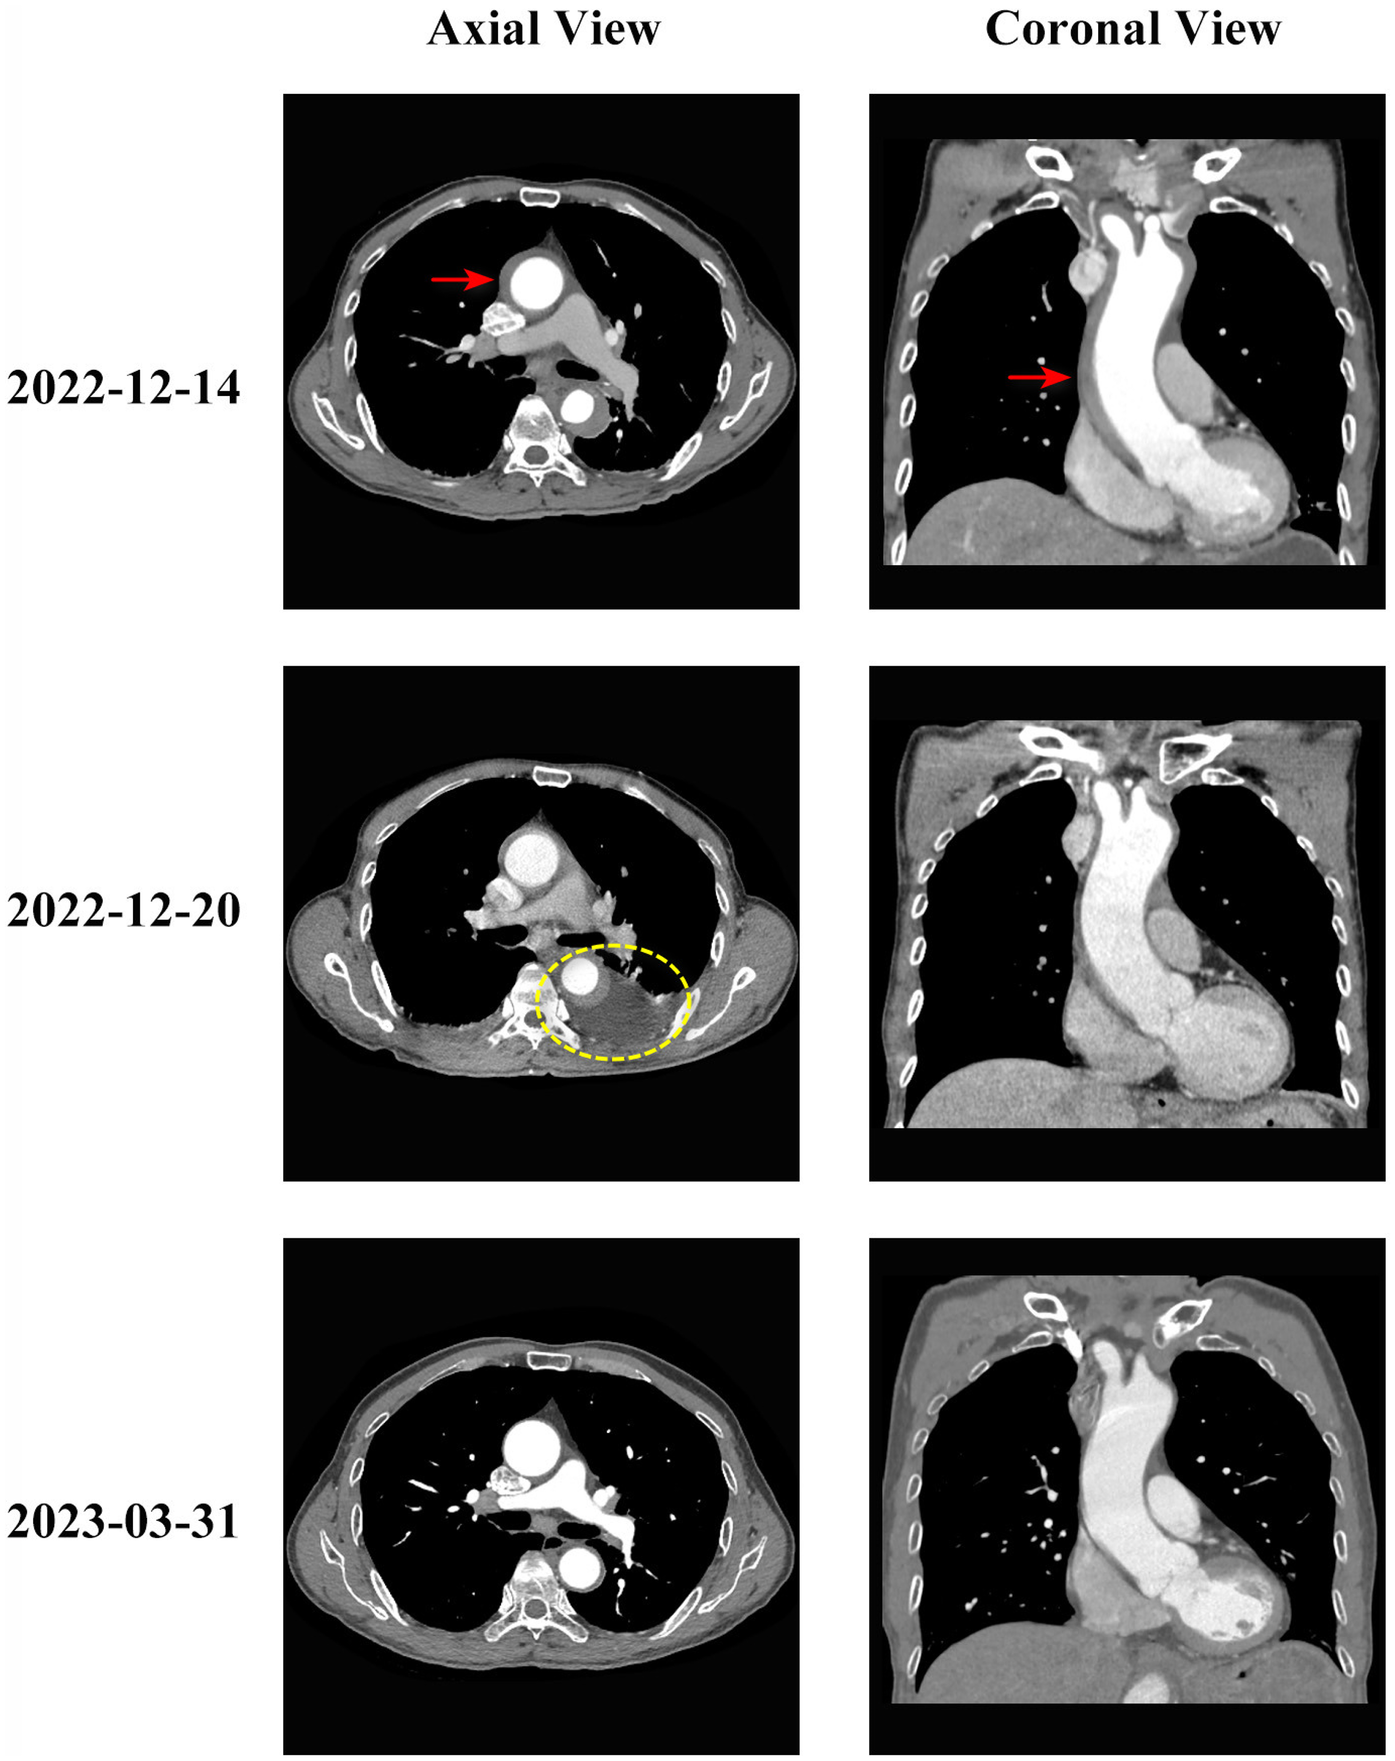

Follow-up CTA one week after treatment showed resolution of the ascending aortic intramural hematoma, but periaortic hematoma was noted in the descending aorta. The patient's chest pain symptoms significantly improved, and vital signs remained stable. Follow-up aortic CTA at 3 months post-discharge demonstrated complete resolution of the ascending aortic hematoma and complete disappearance of the periaortic hematoma. The patient returned to normal activities, and clinical follow-up at 2.5 years showed continued good clinical condition. The typical CT evolution process is shown in Figure 1.

Figure 1

Evolution of type A aortic intramural hematoma during conservative treatment. Serial computed tomography angiography (CTA) images showing the evolution of type A aortic intramural hematoma in axial (left column) and coronal (right column) views. Top row (2022-12-14): Initial presentation showing type A intramural hematoma involving the ascending aorta (red arrows indicate intramural hematoma location) with thickening of the aortic wall (hematoma thickness 7 mm). The ascending aortic diameter measured 42 mm. Middle row (2022-12-20): One weeks after conservative treatment initiation, showing resolution of the ascending aortic intramural hematoma but development of periaortic hematoma around the descending aorta (yellow circle indicates periaortic hematoma). Bottom row (2023-03-31): Three months follow-up demonstrating complete resolution of both the intramural hematoma and periaortic hematoma, with restoration of normal aortic wall appearance. The patient remained asymptomatic throughout the follow-up period.